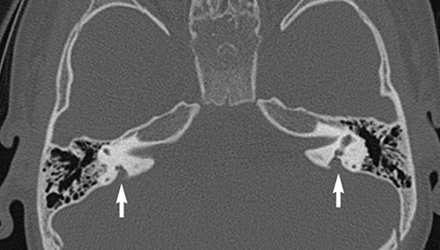

SLC26A4基因定位于人類染色體7q31,SLC26A4基因和大前庭導(dǎo)水管綜合征相關(guān)突變位點的發(fā)現(xiàn),證實SLC26A4是大前庭導(dǎo)水管綜合征的責(zé)任基因。

我們平時提到的“一巴掌打聾”、“一跤摔聾”其實都與SLC26A4基因突變有關(guān),絕大多數(shù)大前庭導(dǎo)水管綜合征都是SLC26A4基因突變?nèi)堑牡湣?/p>

SLC26A4基因編碼一種叫“Pendrin”的跨膜轉(zhuǎn)運蛋白,在機(jī)體離子成分平衡的維持中發(fā)揮重要作用。

在內(nèi)耳,Pendrin表達(dá)于內(nèi)淋巴管、內(nèi)淋巴囊、橢圓囊、球囊等處,異變的蛋白將對這些結(jié)構(gòu)的正常生理功能產(chǎn)生影響,引發(fā)聽損。

SLC26A4基因突變導(dǎo)致的大前庭導(dǎo)水管綜合征的典型表現(xiàn)為兒童時期的聽力損失,90%的患者為雙側(cè)性,聽力損失程度不一,可表現(xiàn)為接近正常或重-極重度。

病程可為穩(wěn)定性、進(jìn)行性或波動性,聽力可逐步下降至全聾;跌倒、撞擊等行為或無外界影響都可能引發(fā)聽力的下降。